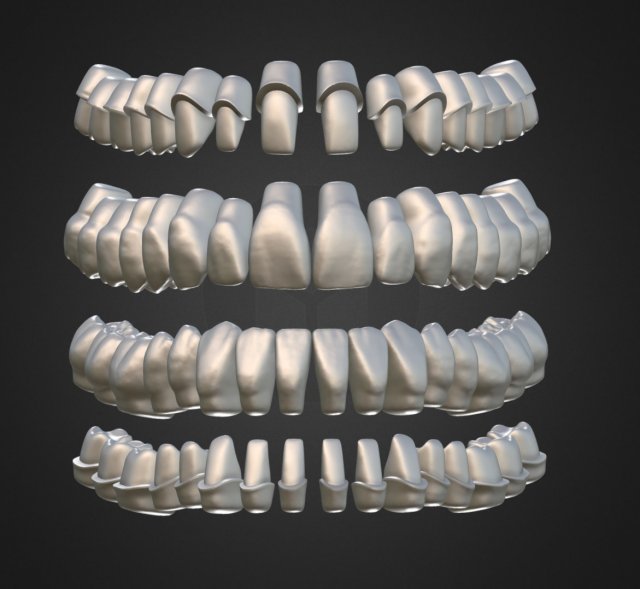

dental anatomy library with thimble crowns - azure Model do druku 3D

dental anatomy library with thimble crowns - azure. position of thimble crowns is same as teeth position. all teeth is separate files. if you want to publish or sell these files please contact me.

dental anatomy teeth tooth morphology jaw skelet exocad cad 3dprint library dentist science medicine mouth toothbrush body printable thimble crownBrak komentarzy dla tego produktu.